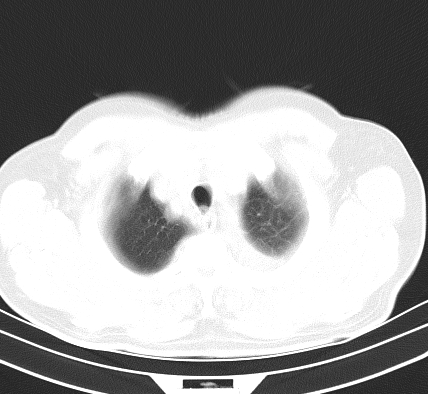

以下是引用老爱克斯新网客在2008-7-31 6:30:00的发言:[br]左肺上叶大片状病灶,左肺上叶支气管狭窄呈鼠尾状,左肺门增大,纵隔内见肿大淋巴结,左侧胸腔积液,余肺清晰。左肺中心型肺癌淋巴结转移,

以下是引用zjzjr在2008-7-31 8:45:00的发言:[br]考虑左侧中心性肺癌伴阻塞性肺炎,左肺上叶肺不张,纵隔淋巴结转移;左侧胸腔积液。建议行纤支镜检查。

以下是引用zjb在2008-7-31 6:32:00的发言:[br]左侧中心性肺癌 阻塞性肺炎 肺不张 胸腔积液 建议气管镜

以下是引用sdzyy在2008-7-31 8:47:00的发言:[br]病灶较治疗前有所进展,胸水增多, 左侧中心性肺癌 并 阻塞性肺炎 肺不张 胸腔积液 可能性大; 建议气管镜检查。 [br] [br]